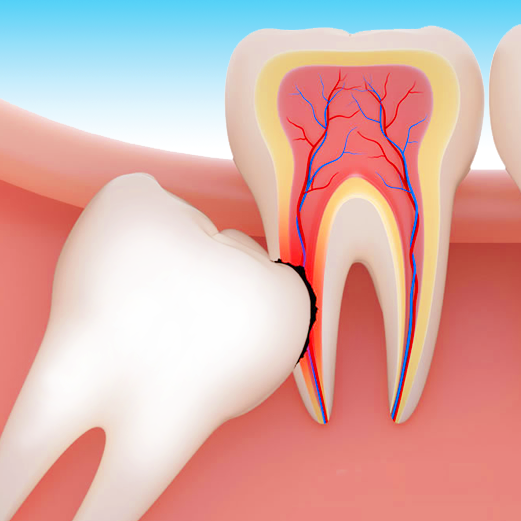

ENDODONTIA

A endodontia é a área da medicina dentária que trata a patologia da polpa dentária e tecidos que rodeiam as raízes. As desvitalizações podem, quase sempre, salvar estes dentes, mantendo a função mastigatória e a estética inalteradas.

CIRURGIA

Dedica-se ao tratamento cirúrgico das doenças, lesões e anomalias dos dentes, boca, maxilares e estruturas anexas, tais como: extrações, exodontia de dentes do siso, implantologia, biópsias, cirurgias endodônticas e tratamentos periodontais.